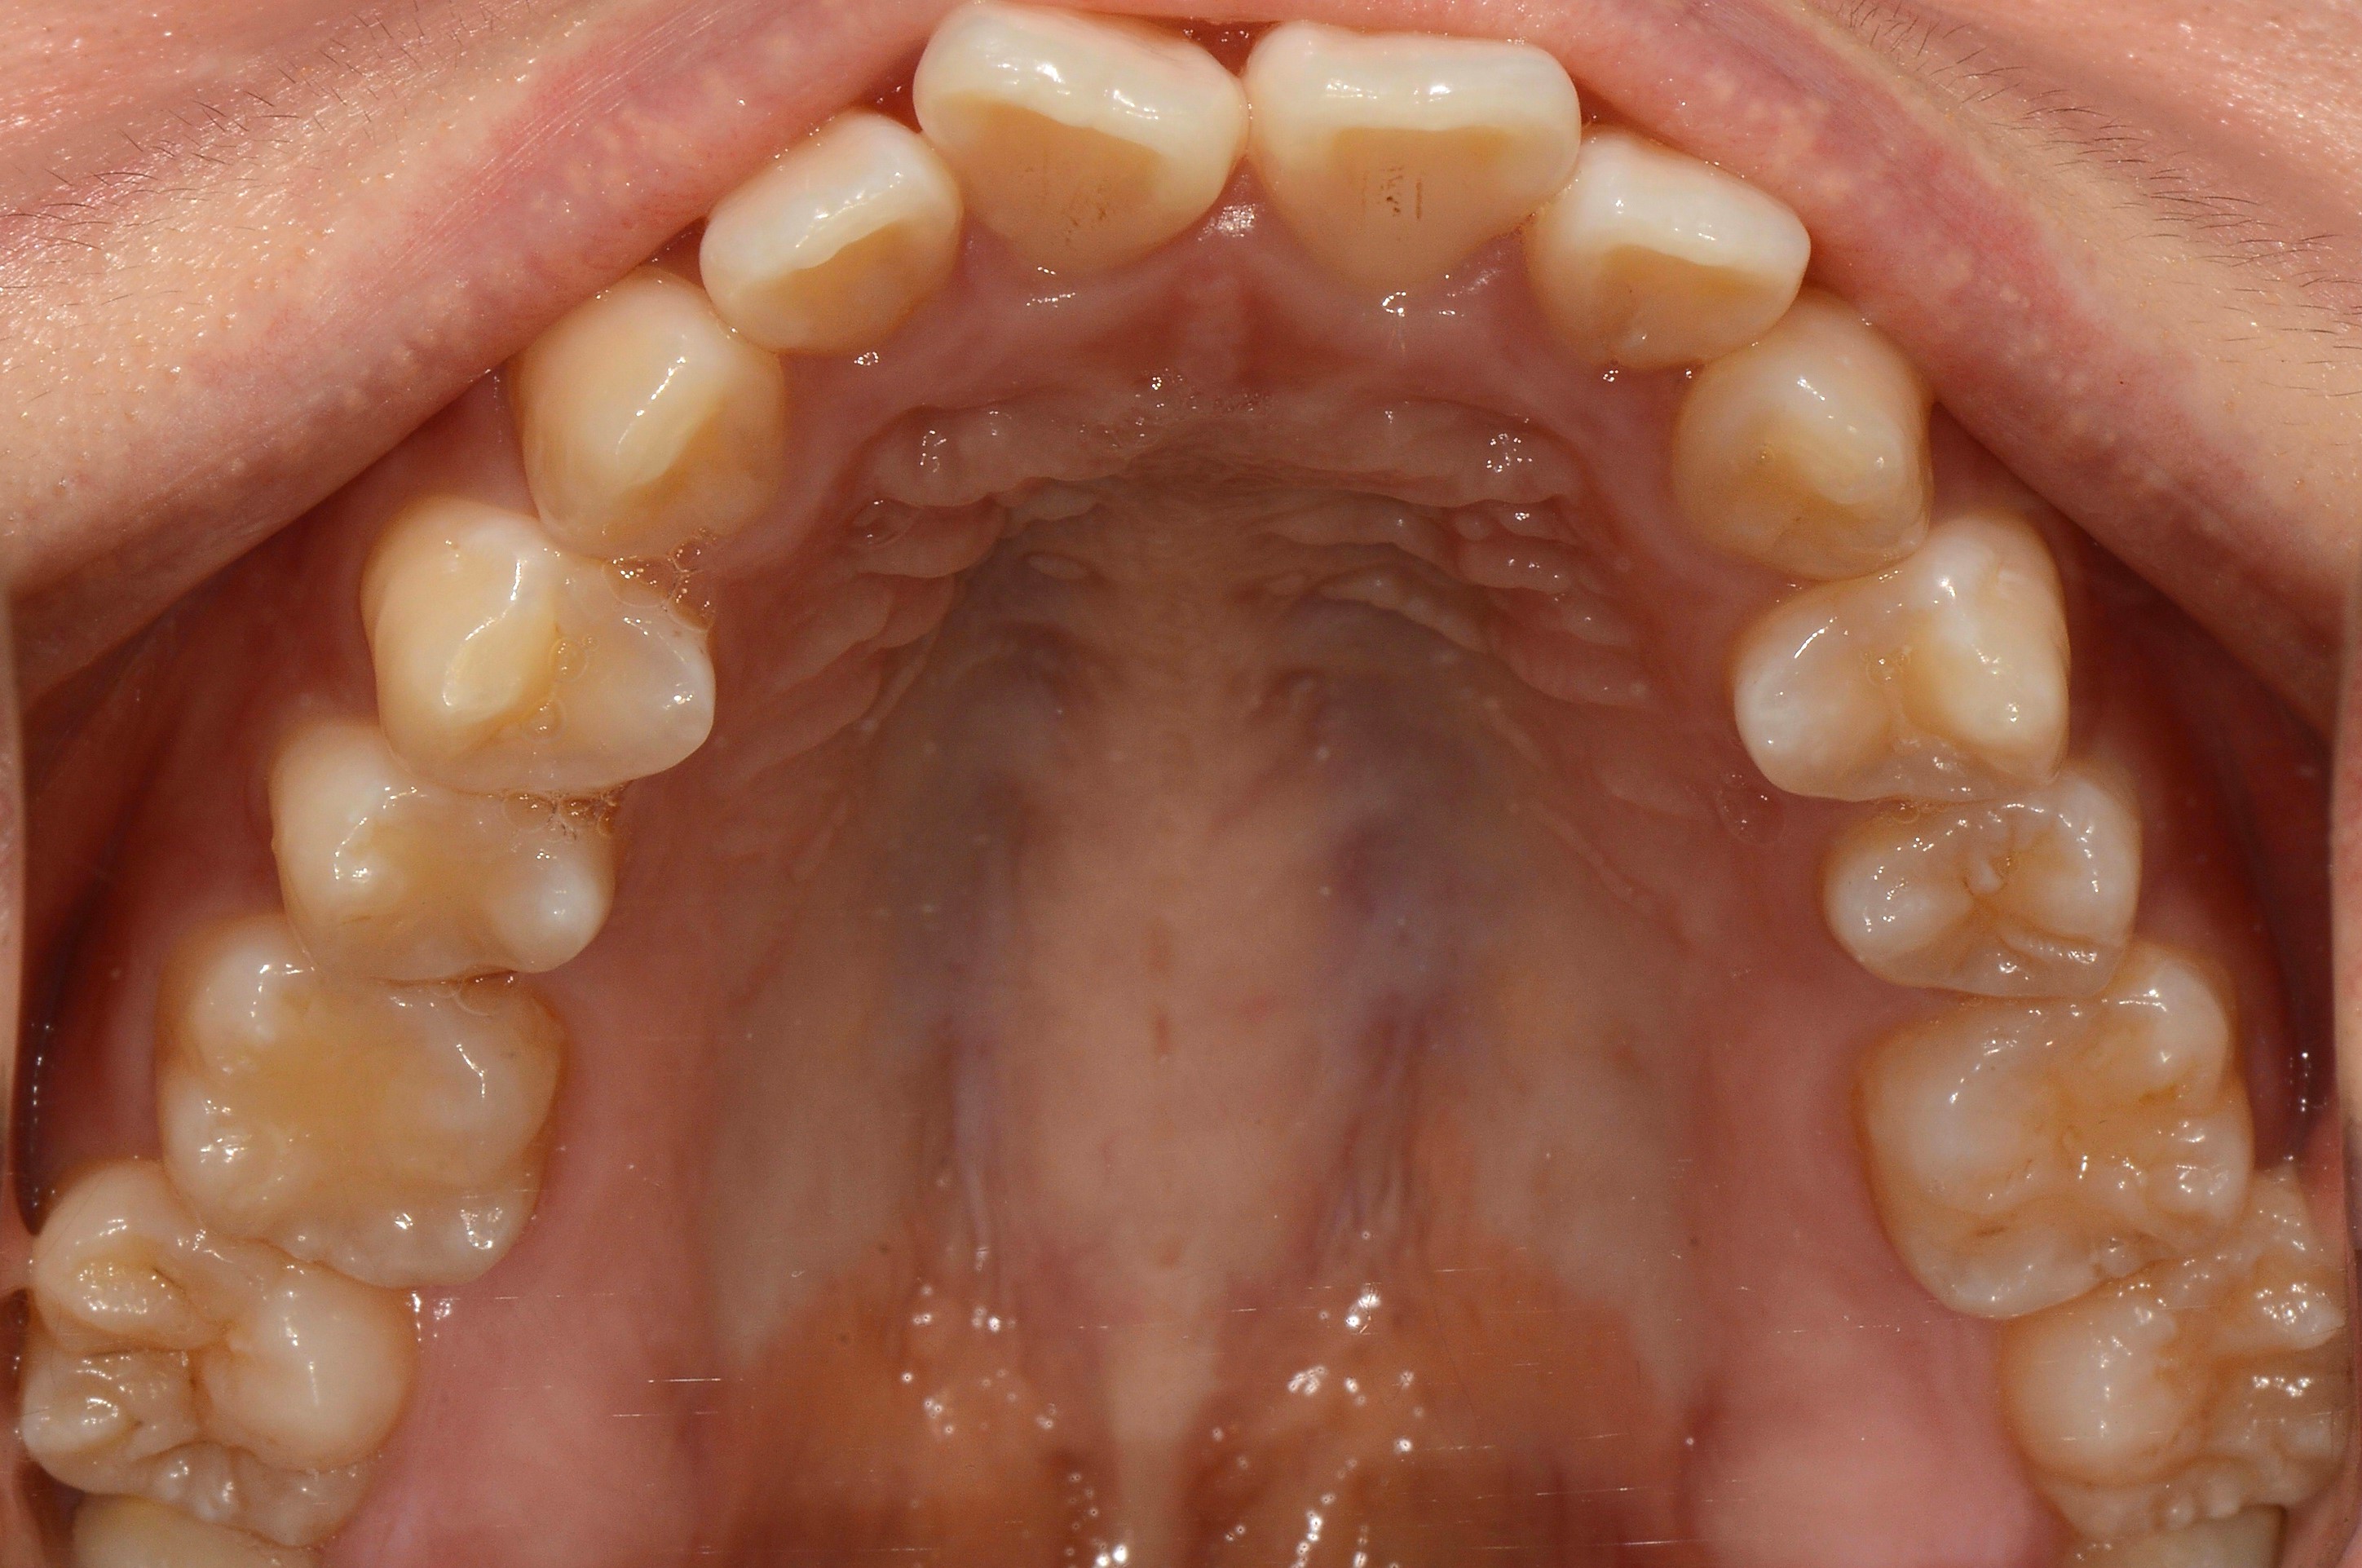

치료 후 사진입니다.